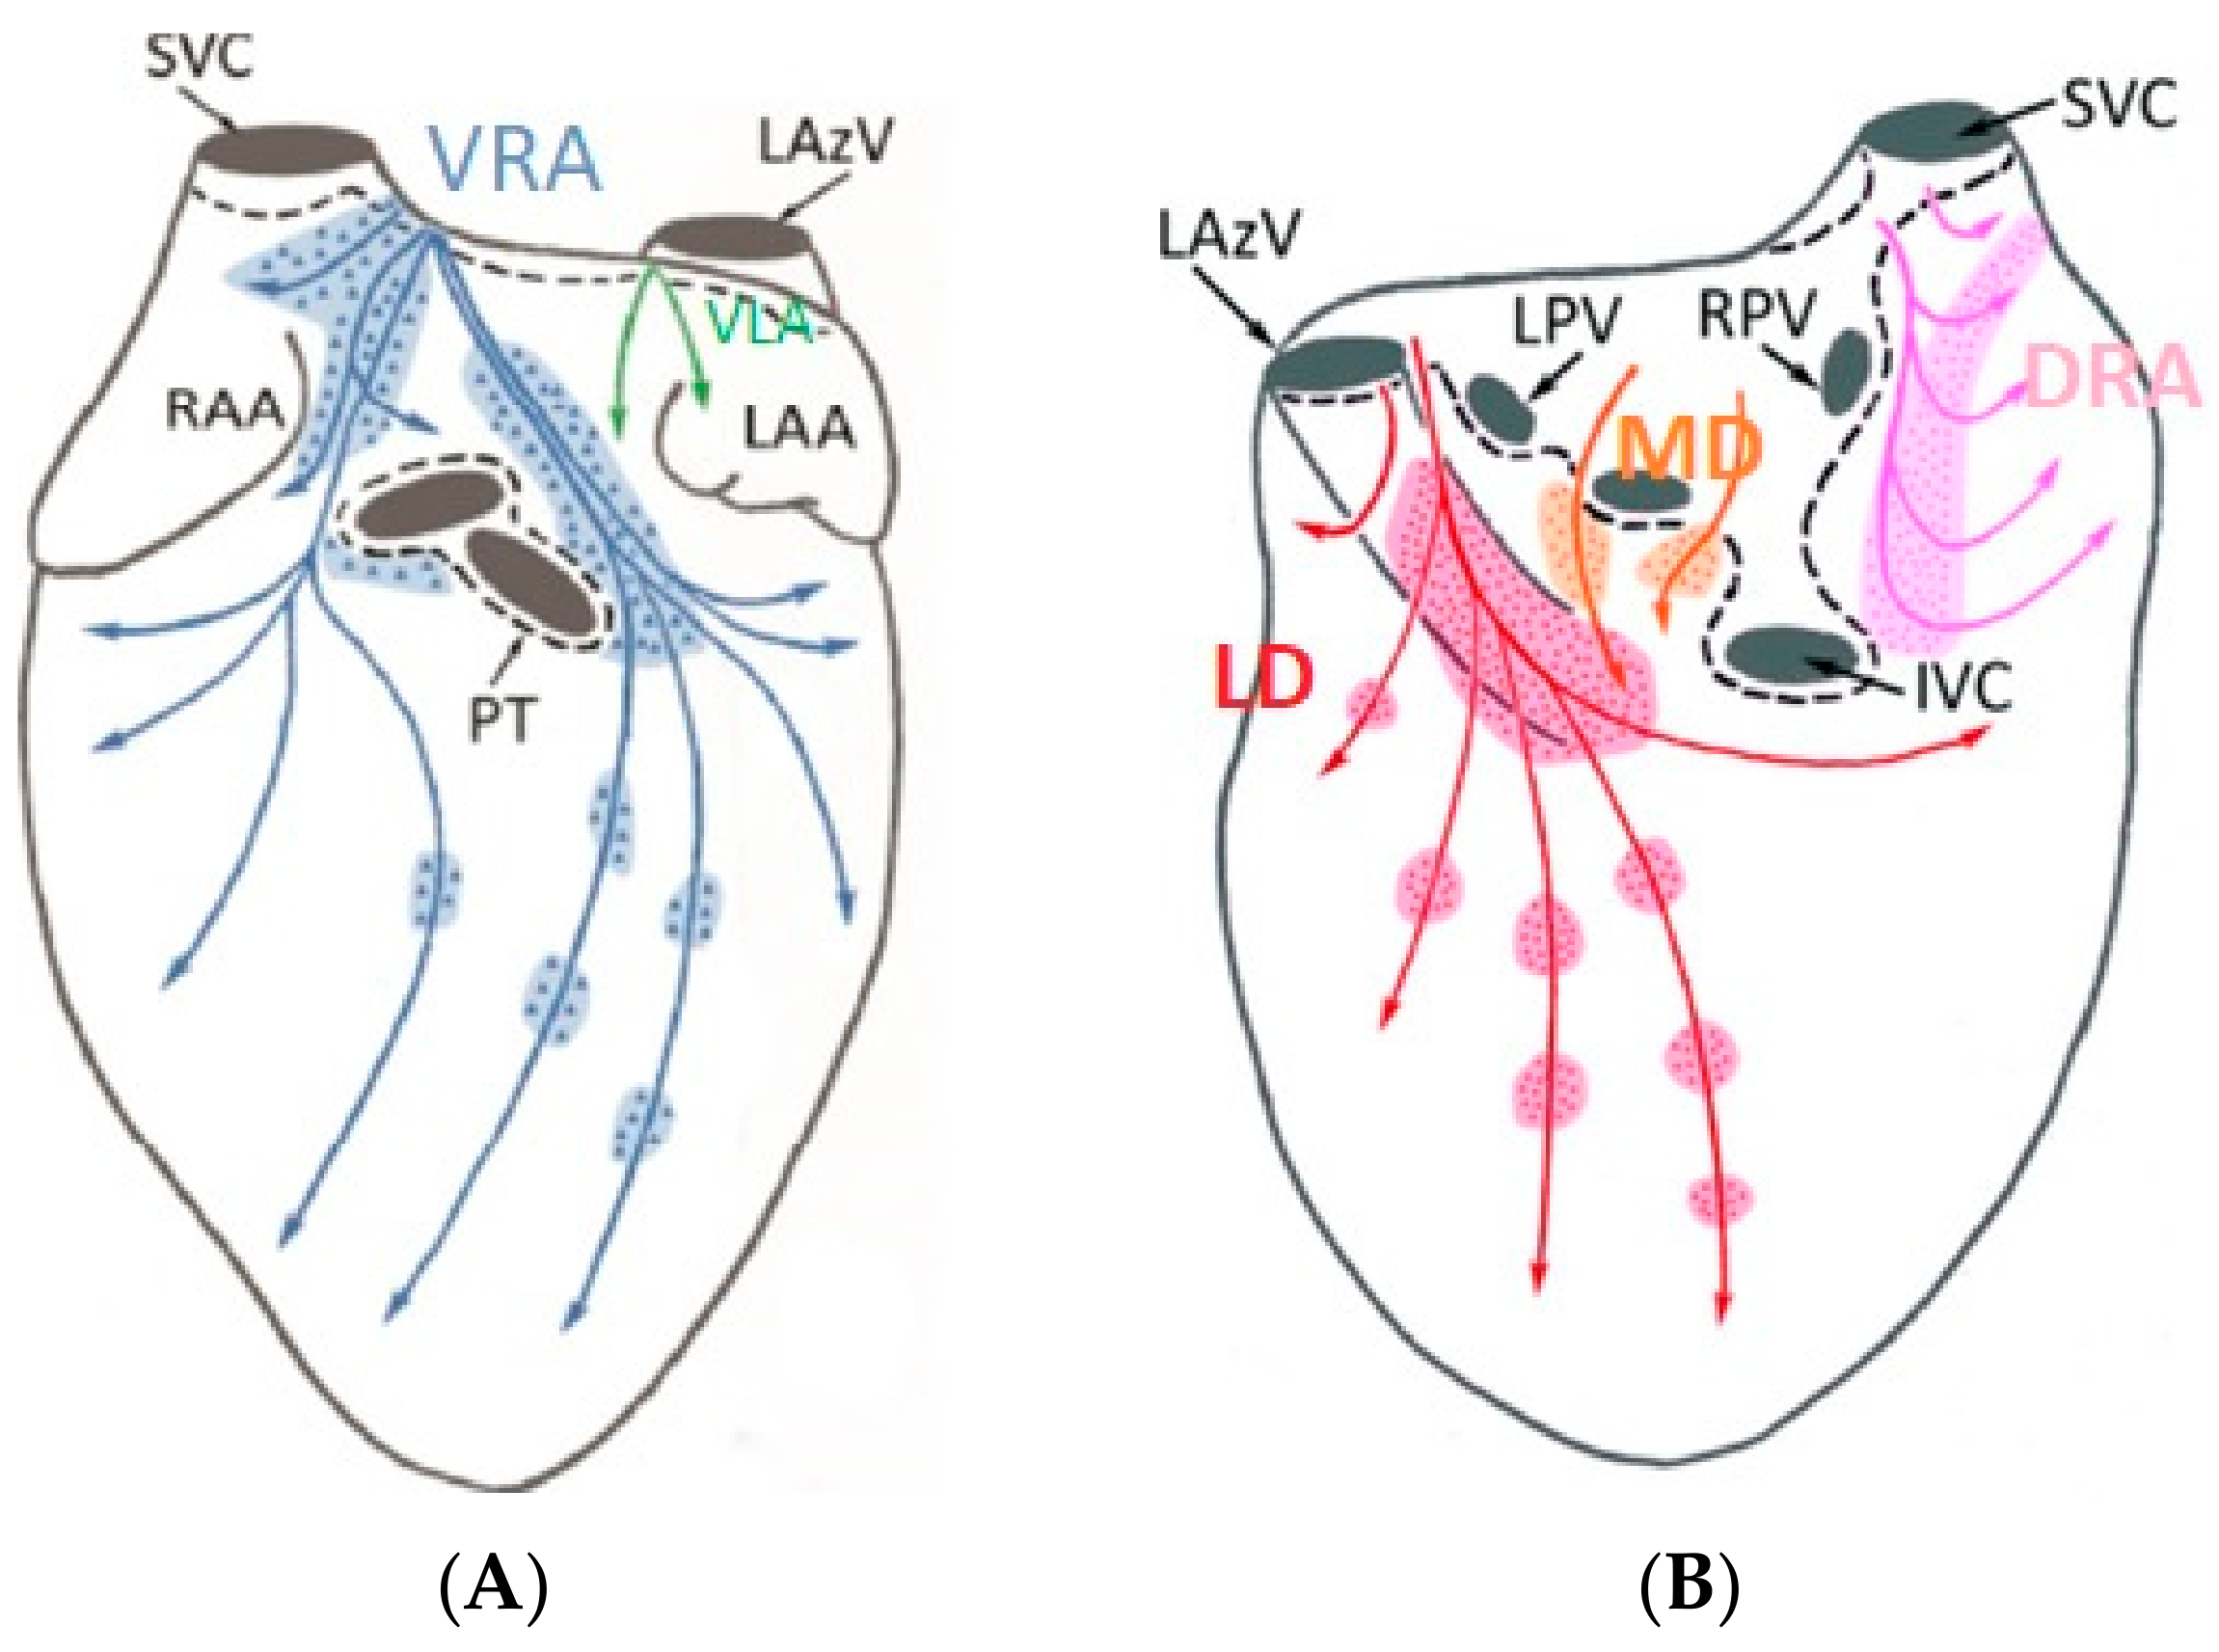

:1. Introduction

3.1. Electric Field Models

4. Discussion